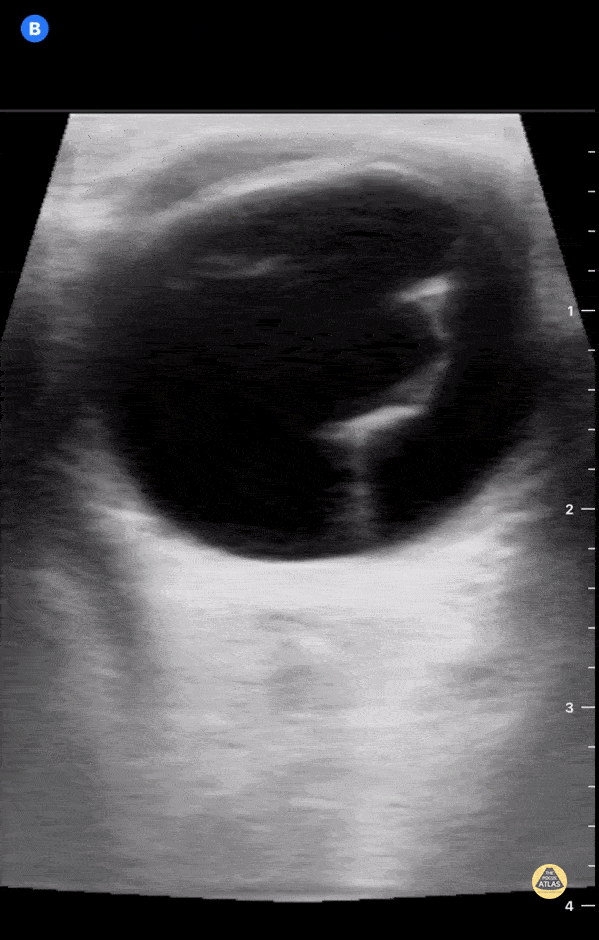

https://www.thepocusatlas.com/ocular

View: Unspecified Parasternal Long Axis Parasternal Short Axis Apical Four-Chamber Subcostal Four-Chamber Subcostal Inferior Vena Cava Right Upper Quadrant Left Upper Quadrant Suprapubic Longitudinal Suprapubic Transverse Subxiphoid Anterior Thoracic Phrenic